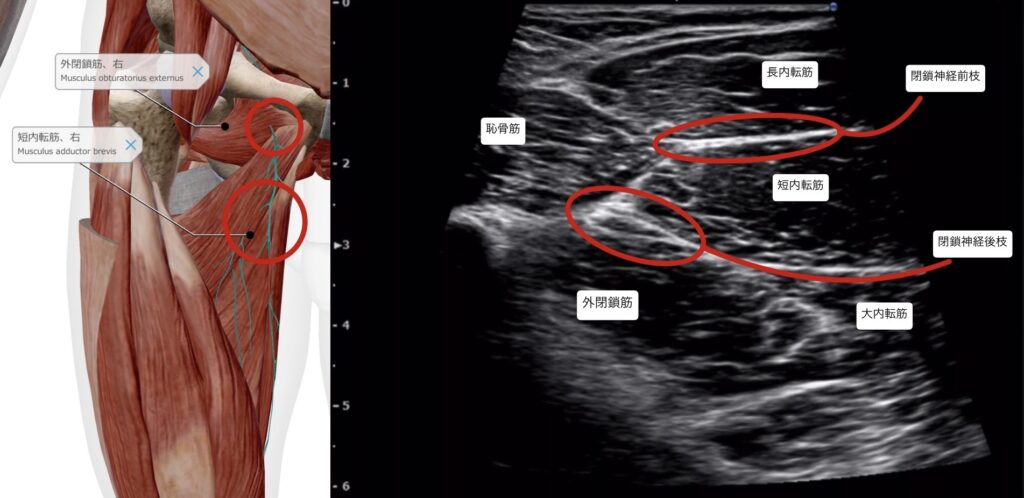

・超音波エコー下の触診で外閉鎖筋~内転筋群の圧痛あり。

・閉鎖神経と外閉鎖筋に対しエコーガイド下で鍼通電を行った。

受傷時に外閉鎖筋肉離れが起きていた可能性が高く、それが原因で閉鎖神経の滑走障害があったと考える。